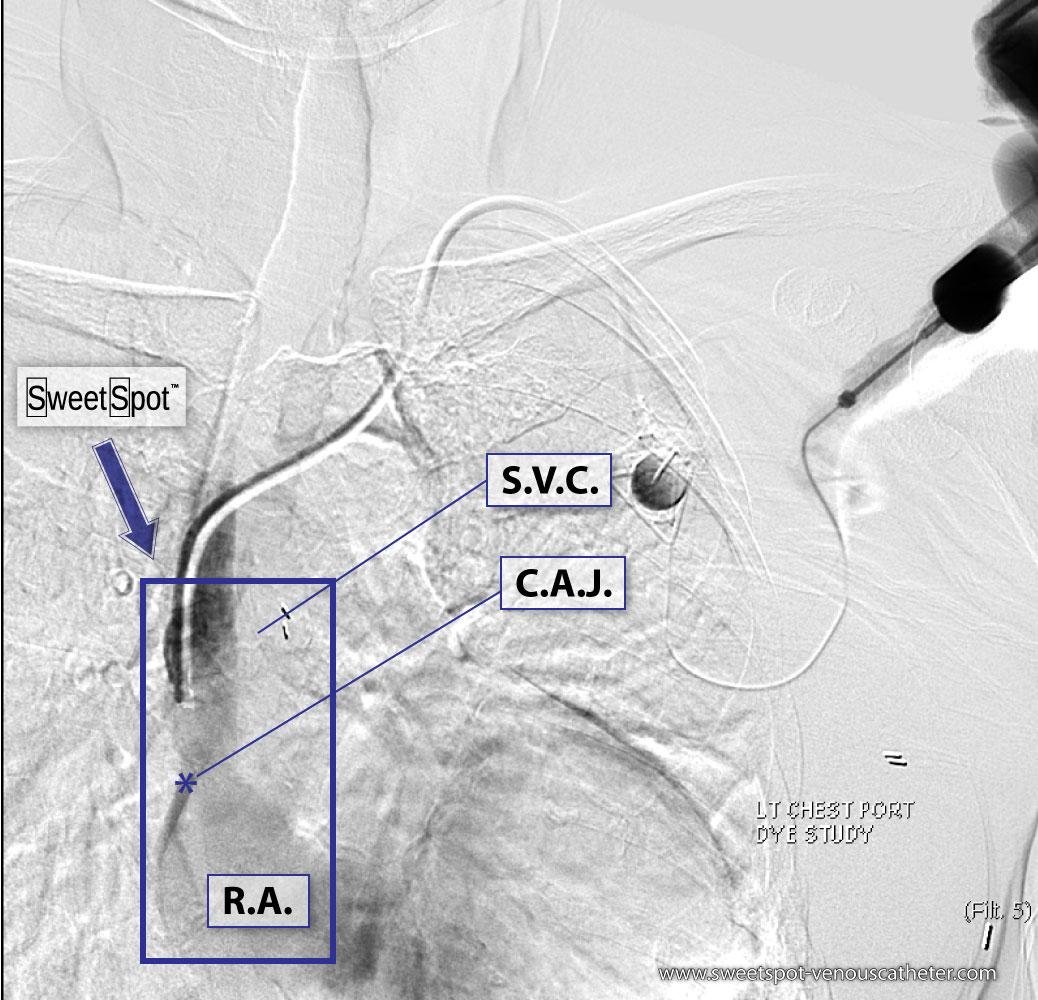

Figure - 07

Left-sided chest port S.V.C. gram (mild fibrin sleeve at distal catheter) |